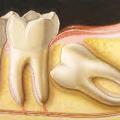

Prosthetique dentaire

Quand une dent est trop endommagée pour la sauvée avec une obturation de la couronne (plombage), elle doit être restaurée par un traitement prothétique.